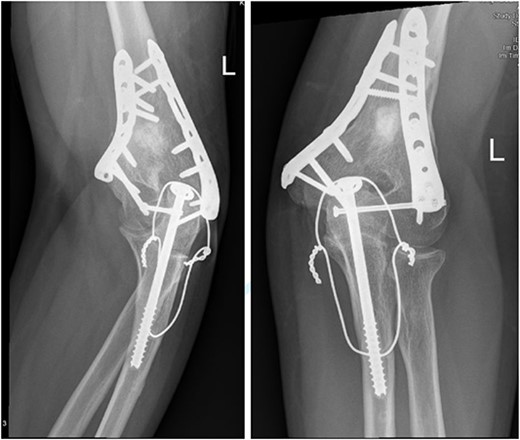

Upon arrival the patient underwent exploratory laparotomy followed by irrigation and debridement of both femur and humerus and application of external fixators (Fig. 2). The patient was admitted to the intensive care unit (ICU). Two days later, the patient underwent open reduction and internal fixation of both proximal and distal humerus (Fig. 3).

Anteroposterior (AP) view of the left humerus and elbow after ORIF.

The patient underwent left open reduction and internal fixation of proximal and distal humerus under general anesthesia. The patient was placed in the lateral position. Preparation and draping in the usual sterile manner were performed and a sterile tourniquet was used. The distal humerus was first approached through a posterior approach. Ulnar nerve protection and olecranon osteotomy was done, showing simple distal intraarticular fracture with minimal metaphyseal comminution. Anatomical reduction of the articular fracture was achieved, with preliminary fixation by k-wires holding the intra-articular fragments. This was followed by interfragmentary screw fixation from medial to lateral. Dual plate fixation (posterolateral and medial anatomical plates) was used to fix both medial and lateral columns, connecting the articular fragment to the metaphyseal. Reduction was confirmed under x-ray. Joint was tested for any screw penetration, and none was found. The osteotomized olecranon was reduced and fixed with cannulated screws and tension bands. The ulnar nerve was protected throughout the whole procedure and was reduced back into the cubital tunnel. Range of motion was examined; full range of motion was achieved. Finally, closure was done in layers.

The patient was then shifted from lateral to beach-chair position, and preparation and draping were repeated. A deltopectoral approach was utilized reaching to the proximal humerus. Reduction was achieved, followed by preliminary fixation with k-wires. Philos plates were used to fix the fracture. Range of motion was examined afterward, with no struggles detected. Fluoroscopic images were taken later to make sure no screws had penetrated the joint. Closure in layers was done, followed by dressing and application of an arm sling.